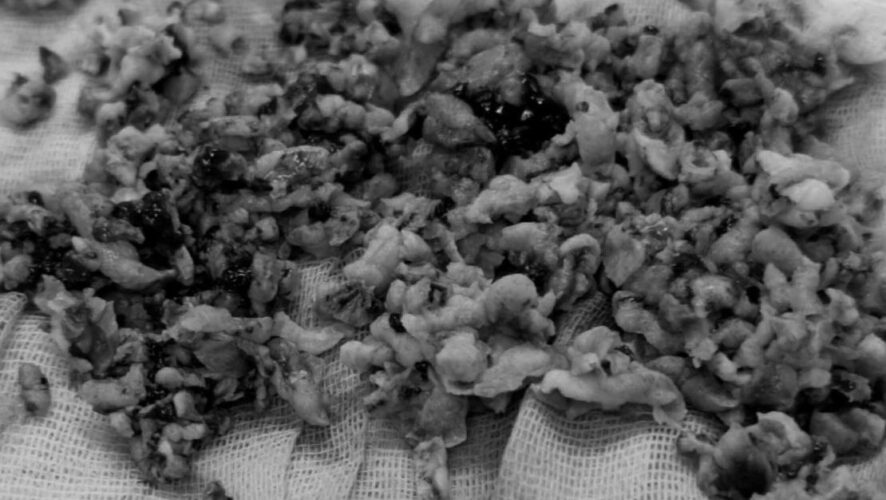

Хирургическое вмешательство, проведенное заведующим урологическим отделением Дильшатом Мухаметшиным и главным хирургом больницы Рустамом Абдурахмановым, было выполнено эндоскопическим методом, без разрезов. Во время операции были удалены сгустки крови, аденома простаты объемом 120 кубических сантиметров (сравнимой с размером мужского кулака) и кровоточащие сосуды.

Операция прошла успешно: кровотечение было полностью остановлено. На четвертые сутки пациент был выписан домой с хорошим самочувствием.